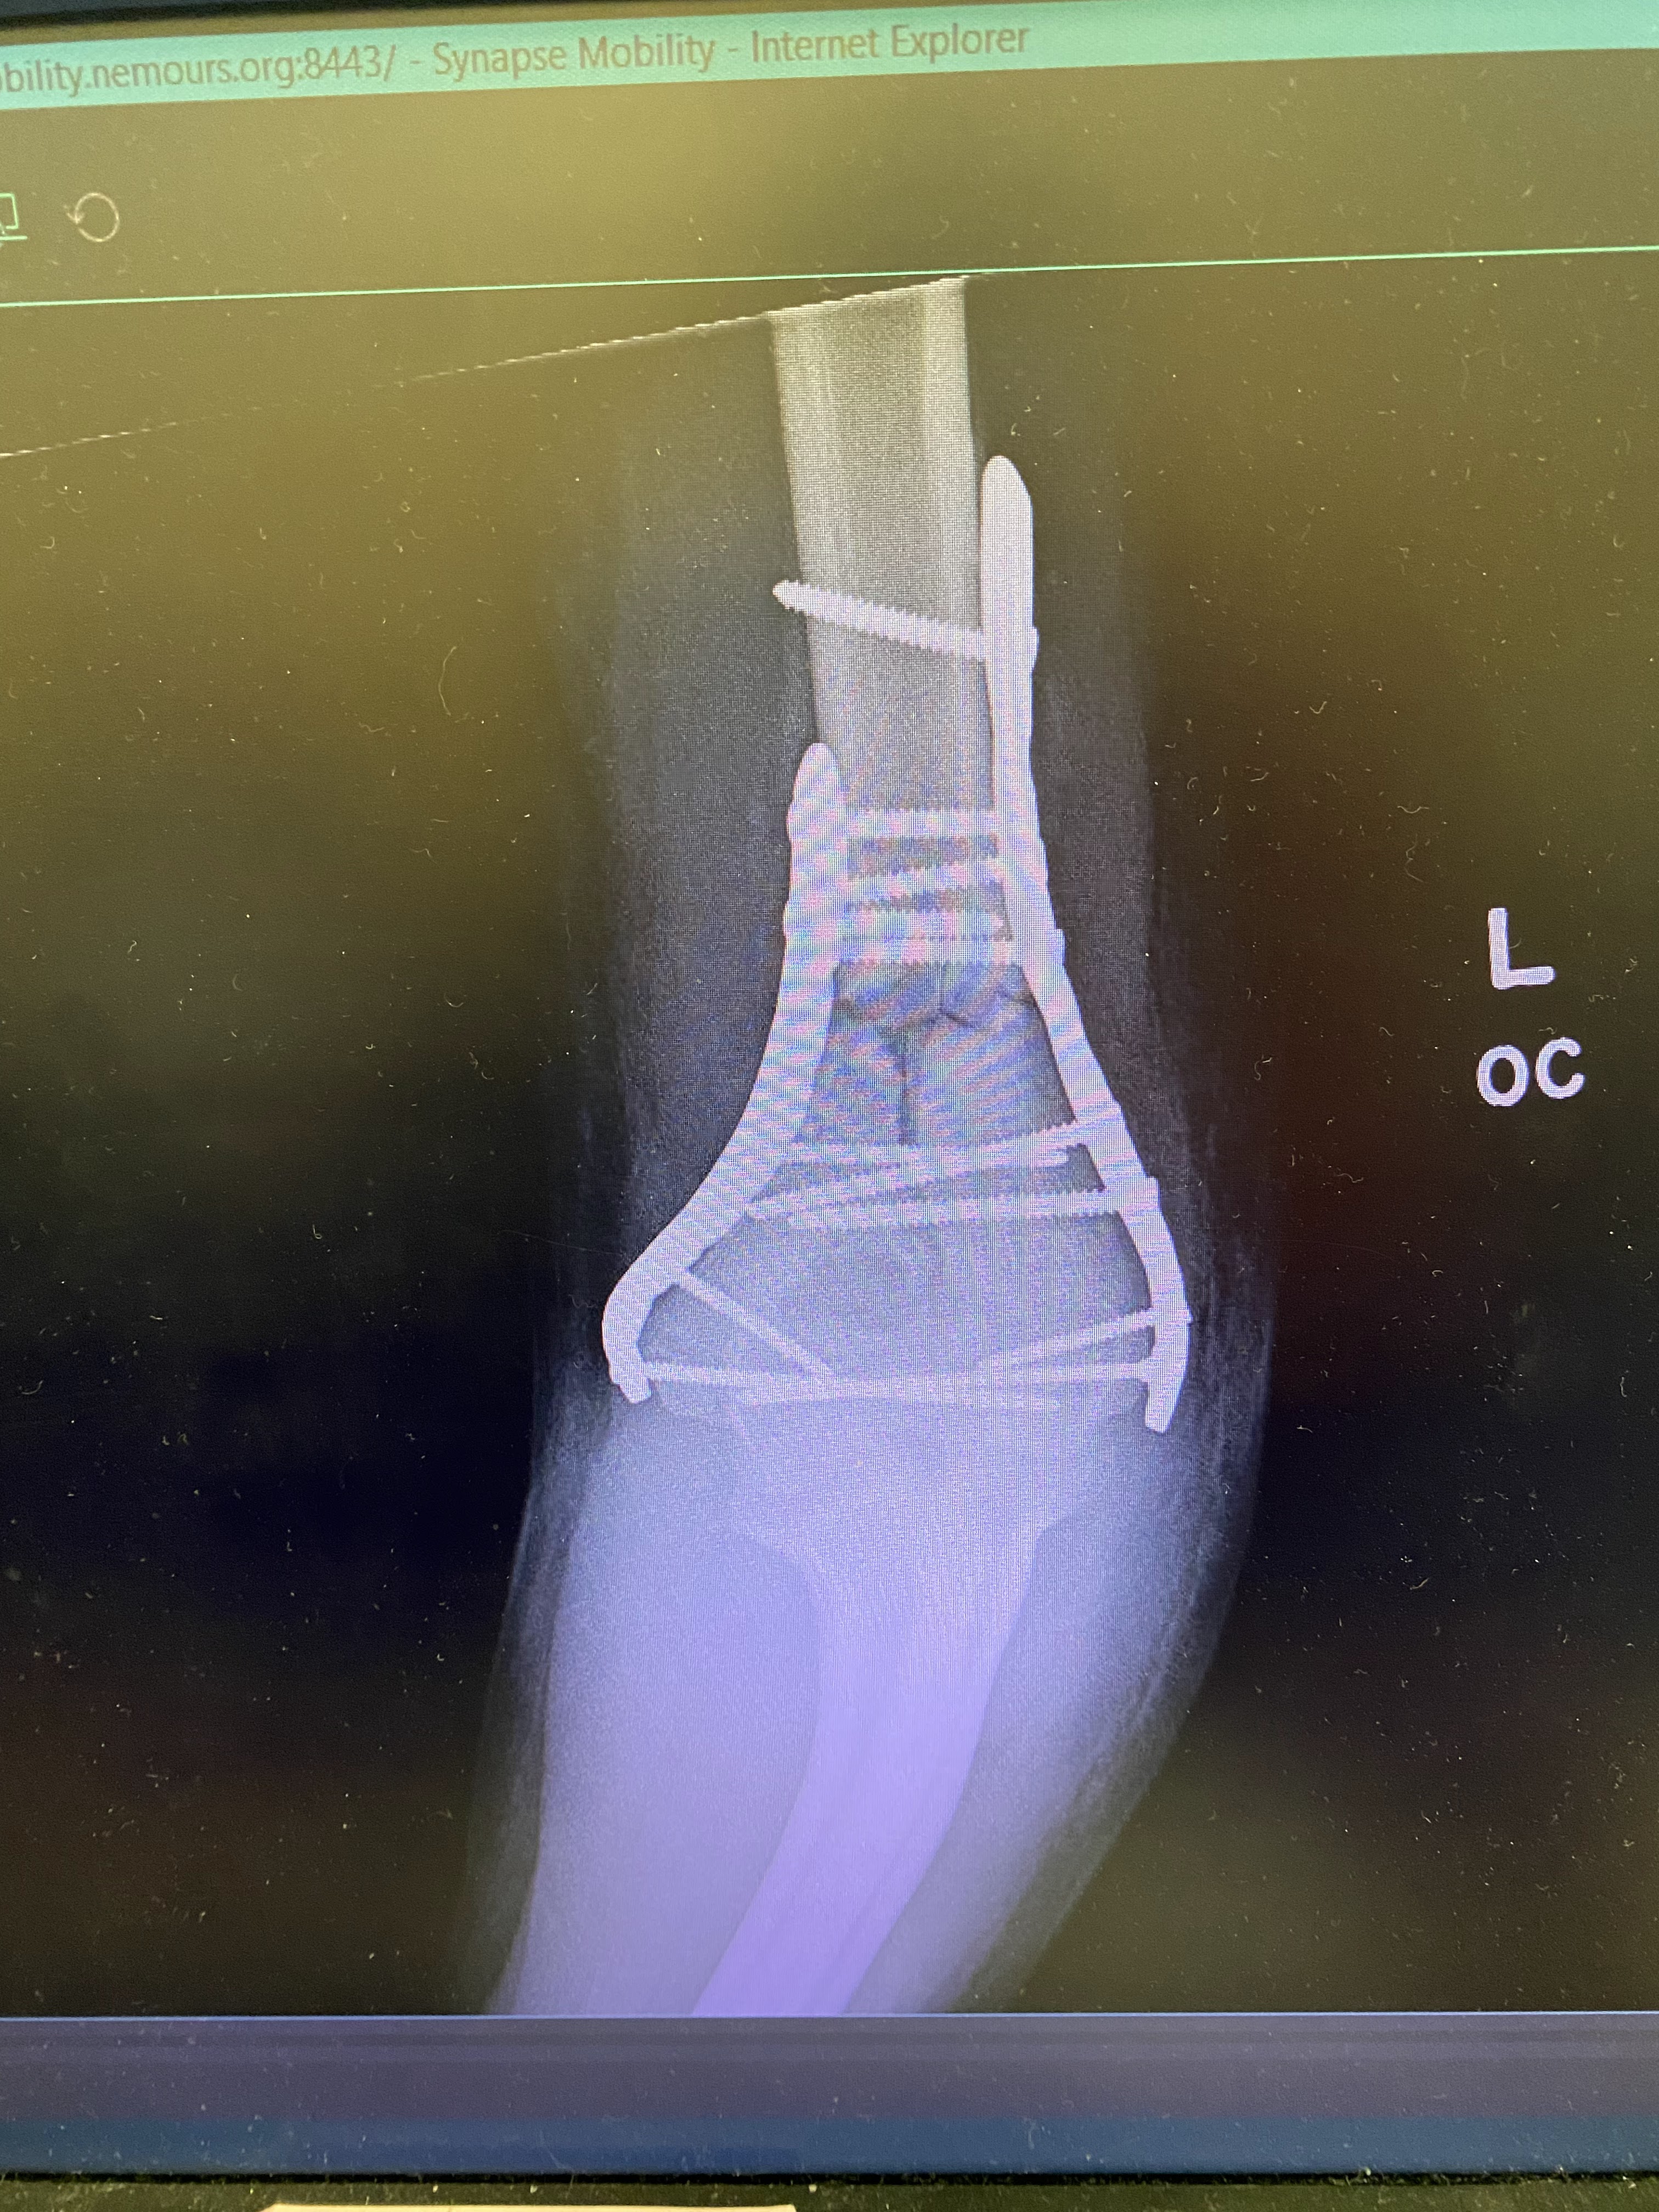

X-rays!

Dr. Baldwin thought surgery would take between 2-3 hours but it ended up taking 5!! They wheeled him away around 10:00 pm and we got a text about 11:00 that they were starting surgery. They were very good about texting us updates regularly and it wasn't until 4:00am that we got a text saying he was all done! The doctor came out to the waiting room to update us personally. She said it was a very difficult surgery but she was very happy with the results. She had to put in 2 plates and 15 screws to rebuild the elbow joint and put the bones back together. As she walked away her back was drenched with sweat and Daniel and I felt so grateful for her hard, diligent work on our boy. Several times in that waiting room I felt prompted to offer up a prayer to lead and guide her and I also felt inspired to ask for angels to be present in the operating room. I felt calm and peaceful that he was being watched over very carefully by many souls. I am grateful for that experience.